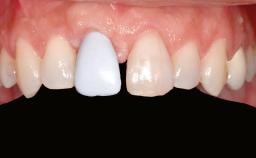

Ridge Preservation and Implant Placement for a Fixed Dental Prosthesis After a Car Accident

Prosthesis Type FDP

Defining Characteristics Up to three missing teeth to be replaced with an implant-borne restoration or restorations

Mesio-Distal Space Anatomic space corresponding to the missing teeth +/- 1 mm